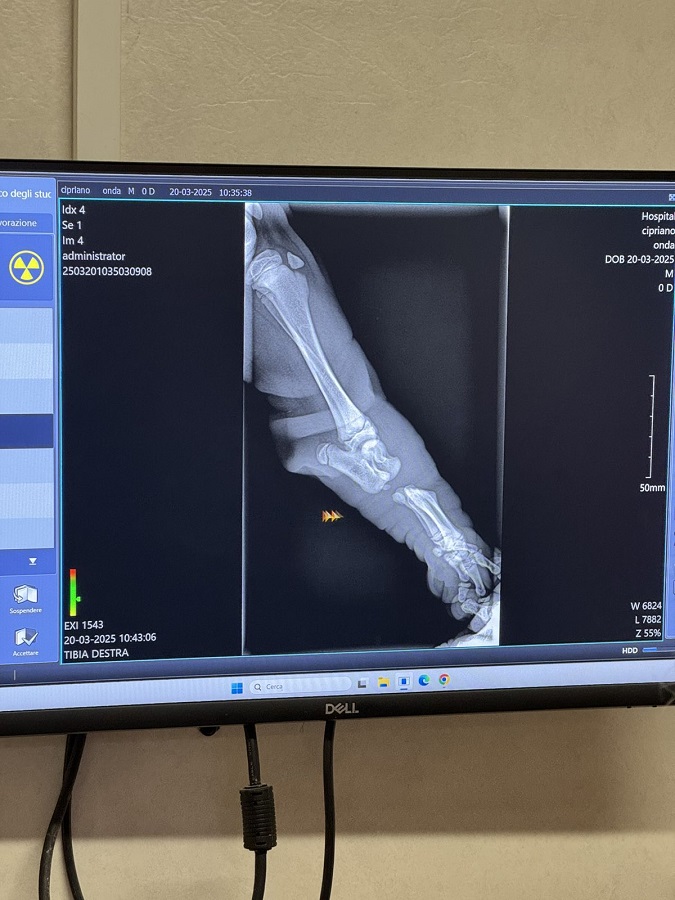

From March 10 to June 6, 202, Oryna LYFAR, a higher education student of the Faculty of Veterinary Medicine, completed an internship at the veterinary clinic of the Italian university. She worked in the departments of therapy and surgery, gaining extensive practical knowledge and skills. This period became invaluable for the academic mobility participant in terms of professional development, offering the opportunity to work side by side with leading veterinarians and apply modern approaches to animal diagnostics and treatment.

In particular, in the surgical department Oryna LYFAR performed the duties of a surgical assistant: she prepared patients for surgery, maintained instrument sterility, participated in surgical procedures, and provided postoperative care. In addition, our university’s representative handled medical documentation, participated in the organization of the treatment process and monitored the implementation of prescriptions. This comprehensive approach allowed Oryna LYFAR to gain a deeper understanding of the specifics of clinical patient management.